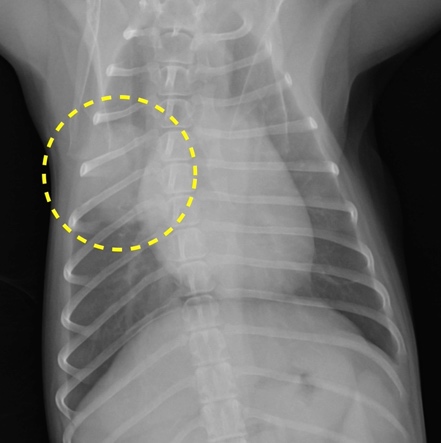

肺の腫瘍

肺癌で多く認められる症状は咳や呼吸が苦しいといった症状ですが、初期には無症状なことも多く、画像検査で偶発的に発見されることも多いです。

犬と猫の両方で最も多い原発性廃腫瘍の種類は腺癌ですが、転移性腫瘍の発生も多いです。

肺の腫瘍が限局し、転移がない場合の治療は外科手術が第一選択です。